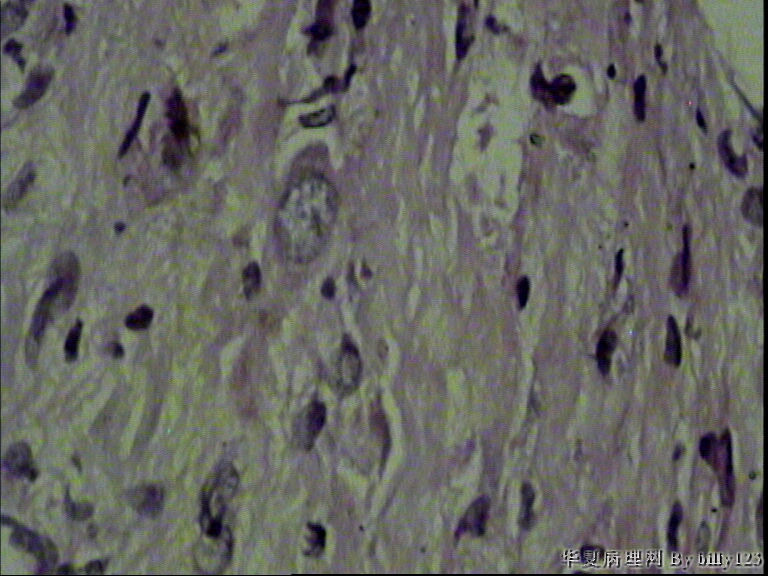

纤支镜活检,女性,75岁,请各位老师指教!

图4